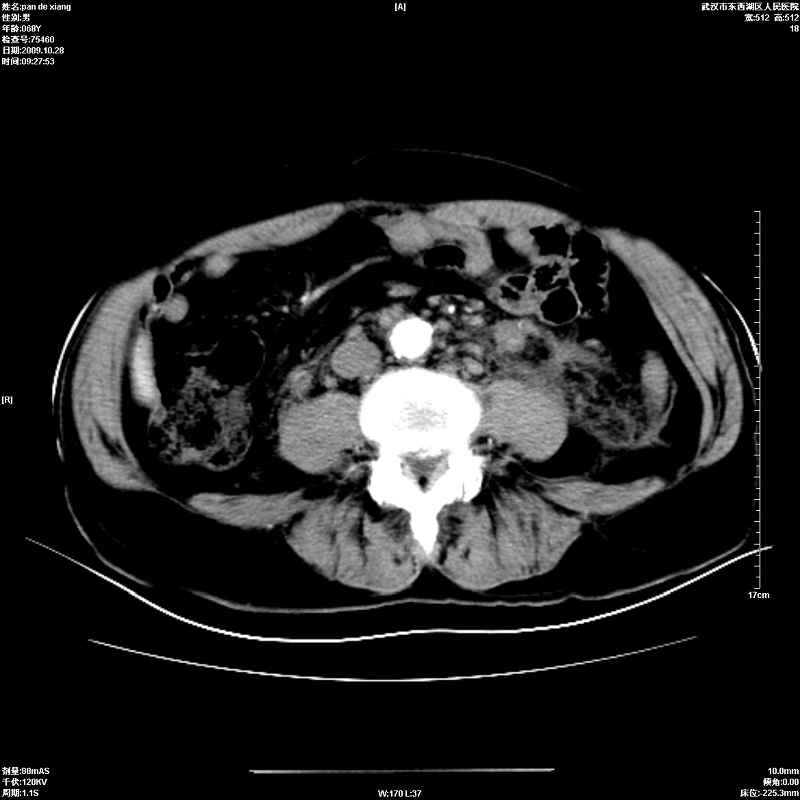

以下是引用杀毒软件在2009-10-28 20:41:00的发言:[br]结合临床考虑---白血病双肾改变或淋巴瘤。

以下是引用zxl51642在2009-10-29 9:59:00的发言:[br]结合临床“单克隆免疫球蛋白血症”,考虑双肾为继发损害并肾功能不全(尿中大量igg及少量iga、igm等大分子免疫球蛋白滤出所致继发损害),椎前软组织肿块为髓外造血。与浆细胞瘤有区别,平扫时有战友说的很清楚。